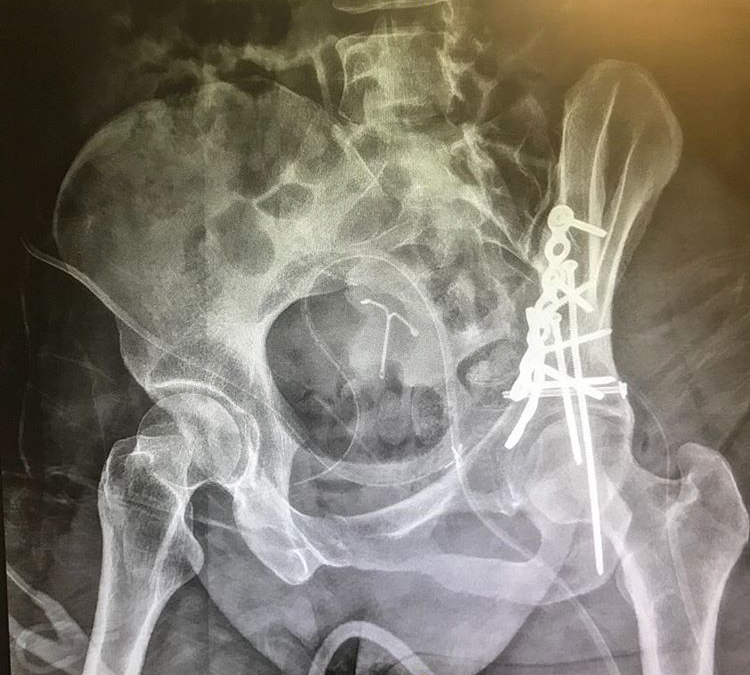

This is what 2 plates, 12 screws and an IUD look like.

Finally, a diagnosis, my pelvis was shattered.  The force sent the ball of my hip straight into the socket which pulverized the bone.  I needed surgery.

I woke up in the recover ward.  Brad was there waiting.  It was 4pm.  Then transport, more x-rays, more transport, another CT scan (The machine died while I was inside and I was left to wait for 20 minutes while they called engineering. It was never repaired), more transport, more time with Manny.  This time, Manny he didn't stop with compliments, he decided I needed to be touched.  I was completely alone and helpless.  I was sobbing as he touched me.  I had no way of calling for help.  I begged for anyone to call Brad who was waiting for me to return.  After almost 3 hours disconnected from all pain meds and too much time with Handsy Manny,  I was finally transported to a room of my own where Brad & Barb were waiting to put me to bed.  The surgery was successful.  The surgery they said I might not need.  The 8+ hour surgery that produced a 10 inch incision, two metal plates and at least a dozen screws to reconstruct my pelvis.